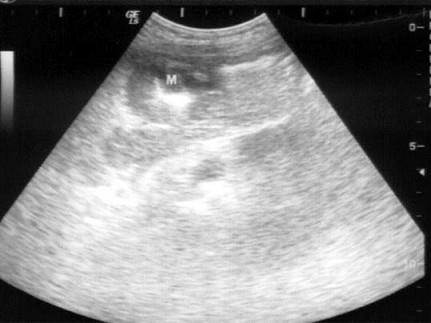

问题 患者女76岁,上腹部胀痛不适半年余,加重1周。剑突下B超检查如图所示,根据超声声像图诊断为?(?)

选项 A.胃癌 B.胃溃疡 C.肾癌 D.结肠癌E、胃炎 E.胆总管蛔虫

答案 A